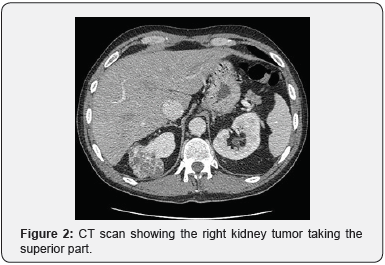

The survey was by CT without injection and MRI as the patient developed renal failure. Two years after nephrectomy, the imaging revealed two suspicious pancreatic nodules, on the body and the tail measuring 3 and 1cm respectively (Figure 2).